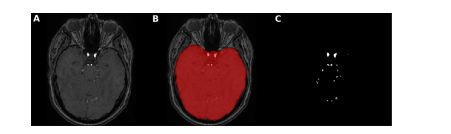

Fig. 3. Brain mask application for intracranial vessels analysis. Here, an axial slice is shown of A. TOF-MRA image with skull B. brain mask extracted using FSL-BET tool from TOF-MRA image C. ground truth segmentation label after brain mask application leading to skull-stripping i.e. removal of all vessels of face and neck with only intracranial vessels remaining

图 3. 用于颅内血管分析的脑部遮罩应用。这里展示了 A. 带有头骨的 TOF-MRA 图像的轴向切片 B. 使用 FSL-BET 工具从 TOF-MRA 图像中提取的脑部遮罩 C. 应用脑部遮罩后的地面真实分割标签,导致去除头骨,即移除面部和颈部的所有血管,只剩下颅内血管。